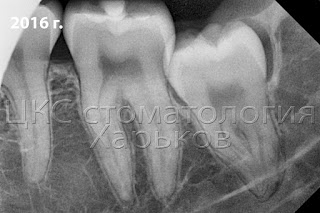

10 лет назад зуб мудрости был с несформированной корневой системой. Теперь корни длинные. У восьмерок они часто причудливой формы, извлекать их намного сложнее.

![]() |

| Рентгенограмма зуба мудрости |